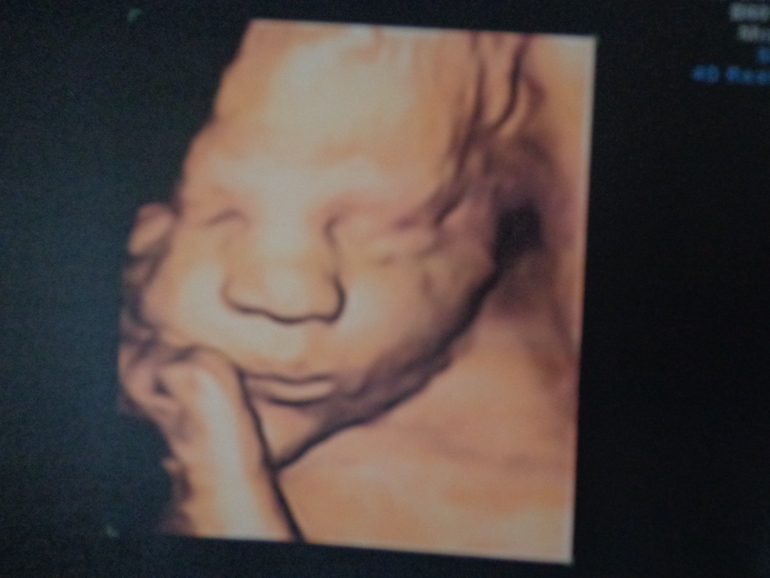

Сделал мне отличную фотографию

Но я четко смотрела на монитор узи и запомнила что ОГ на 40 недель, ОЖ на 41 неделю....Вес ребенка 3800!!!!!!!!